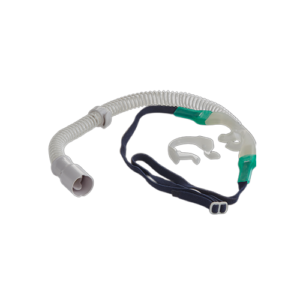

50-05-179, 50-05-172, 50-05-178

Maxflow Adult Nasal Cannula delivers precisely controlled, heated, and humidified air–oxygen mixtures at high flow rates to support spontaneous breathing during high flow oxygen therapy.